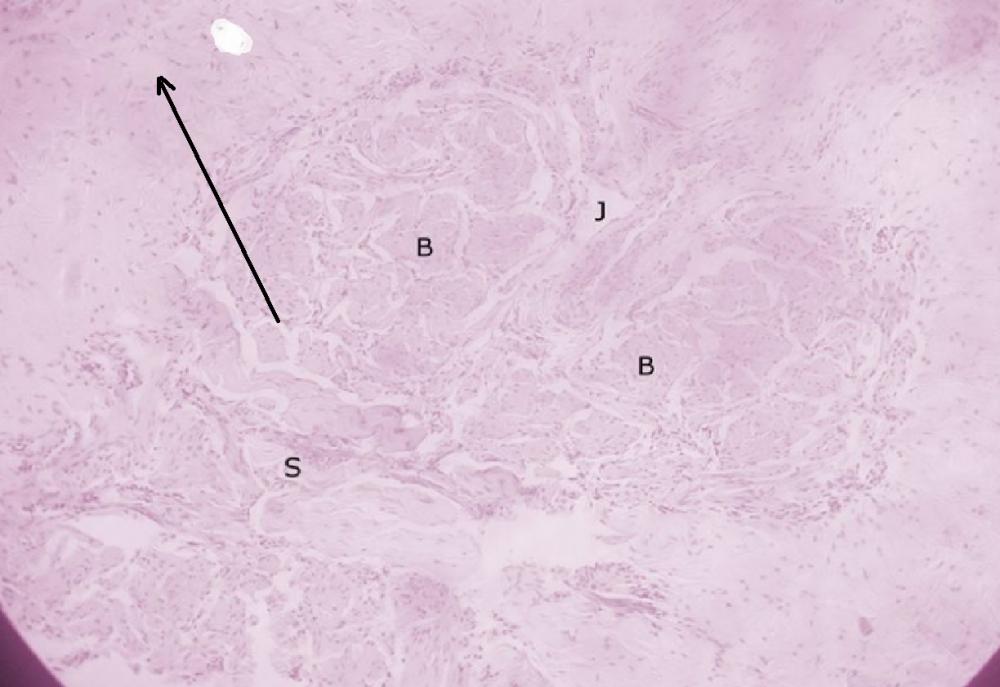

Pytanie 688

kosmki III-rzędowe (łożysko, płyta kosmówkowa)